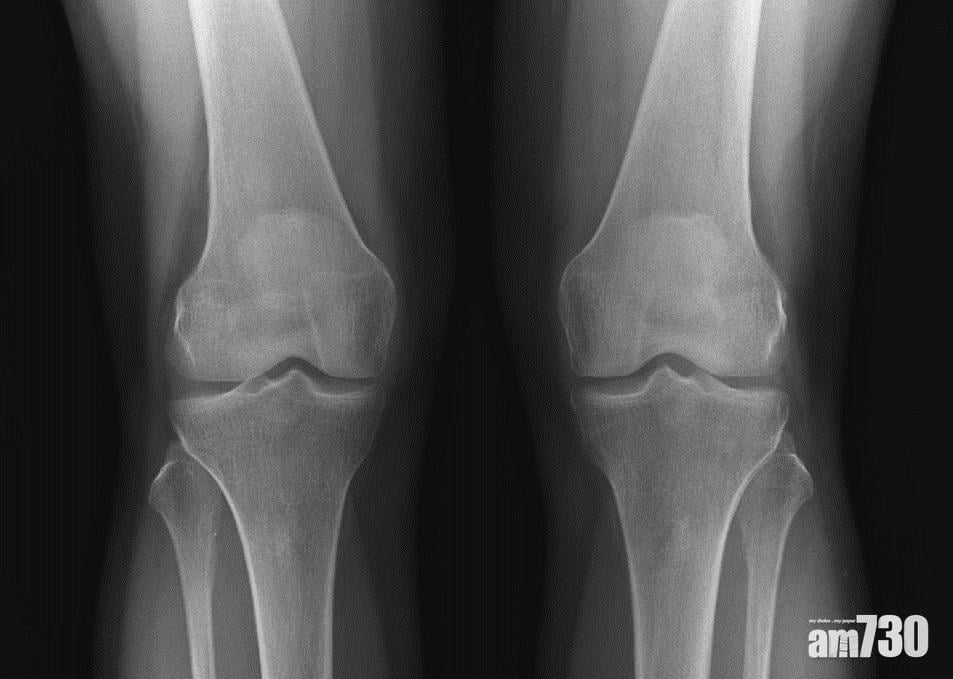

當膝關節的軟骨嚴重磨蝕,甚至出現骨磨骨情況,屆時患者就要接受關節置換手術。李醫生指出,過去較常用的「全膝關節置換手術」,成效顯著,但它的缺點是,即使患者不是整個關節出現退化,也得把全個關節換走,一併把正常組織完全移除,對患者而言並非最大效益,故衍生出「半膝關節置換手術」,只換走需要移除的部份,保留健全的組織。

退化性關節(左)的軟骨層遭磨蝕,距離較正常的關節(右)少,嚴重可出現骨磨骨的情況。(圖片由醫生提供)